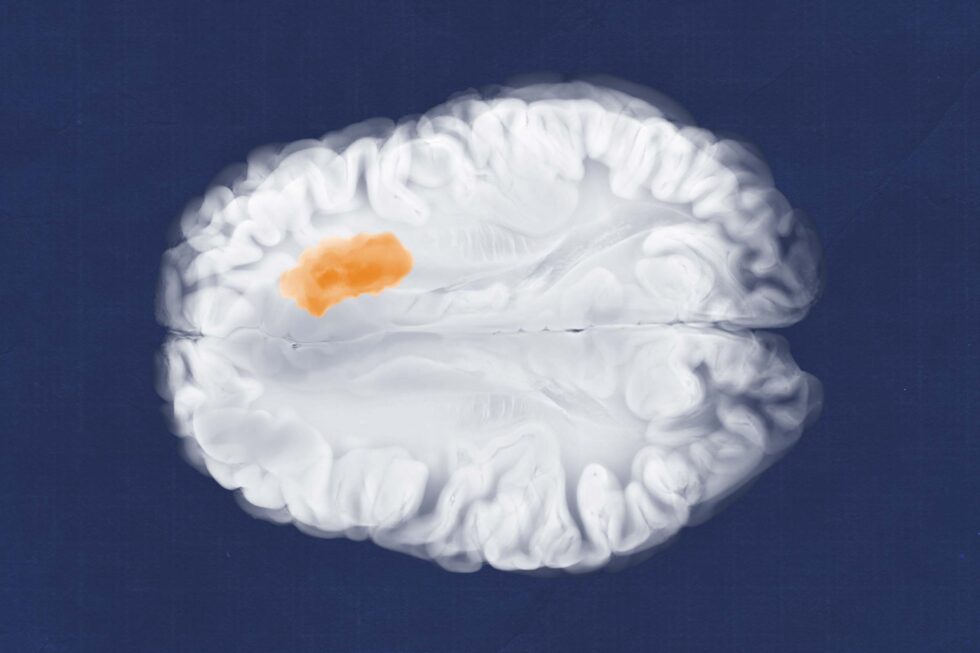

Una possibile svolta contro il glioblastoma, il tumore cerebrale più aggressivo e letale, arriva da un gruppo di ricerca dell’Università della Virginia. Gli scienziati dell’UVA Cancer Center hanno individuato una piccola molecola capace di bloccare un gene chiave che alimenta la crescita del tumore. Il lavoro è stato finanziato dai National Institutes of Health e dalla Ben & Catherine Ivy Foundation e pubblicato su Science Translational Medicine.

Il glioblastoma è una delle diagnosi oncologiche più dure. La sopravvivenza mediana è di circa 14-16 mesi anche con trattamento. Negli Stati Uniti si registrano oltre 14.000 nuovi casi ogni anno. A livello globale i tumori maligni del sistema nervoso centrale superano i 250.000 nuovi casi annui e il glioblastoma rappresenta la forma più comune e aggressiva negli adulti. In Italia i tumori del sistema nervoso centrale causano circa 6.000 nuove diagnosi l’anno. Il glioblastoma costituisce quasi la metà dei tumori cerebrali maligni dell’adulto, con un’incidenza stimata di 3-4 casi ogni 100.000 abitanti. La sopravvivenza a 5 anni resta inferiore al 10 per cento nonostante chirurgia, radioterapia e chemioterapia. Il tumore infiltra il tessuto cerebrale e rende impossibile una rimozione completa. Le terapie disponibili possono estendere la vita di pochi mesi e spesso incidono pesantemente sulla qualità della vita.

Nel 2020 il gruppo di Li ha identificato l’oncogene AVIL come motore della malattia. Questo gene, normalmente coinvolto nella struttura cellulare, quando è iperattivato favorisce la trasformazione tumorale. La proteina prodotta da AVIL è quasi assente nel cervello sano e molto presente nel glioblastoma, una caratteristica che la rende un bersaglio terapeutico ideale. Attraverso screening ad alto rendimento i ricercatori hanno testato migliaia di composti fino a individuare una molecola capace di colpire selettivamente le cellule tumorali e attraversare la barriera ematoencefalica, una delle principali difficoltà nello sviluppo di farmaci neurologici. In prospettiva potrebbe diventare anche una terapia orale.